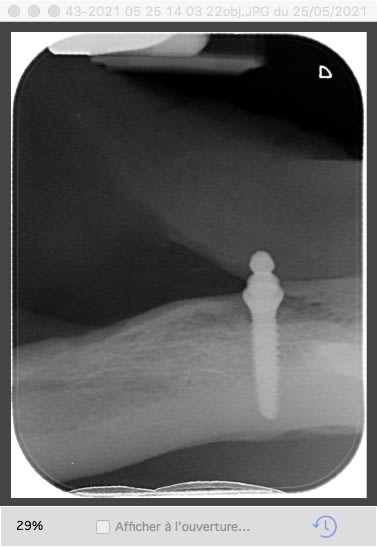

Patiente qui arrive avec son complet sur implant cassé en deux.

Pb ses implants ont été posés au Portugal et la patiente ne connaît pas la marque de ceux-ci. Et je doit changer les bagues de rétention des parties femelles.

çà ressemble fort à un OBI ETK....mais ta radio est pas top top....

J'ai eu confirmation par ETK, c'est bien des OBI